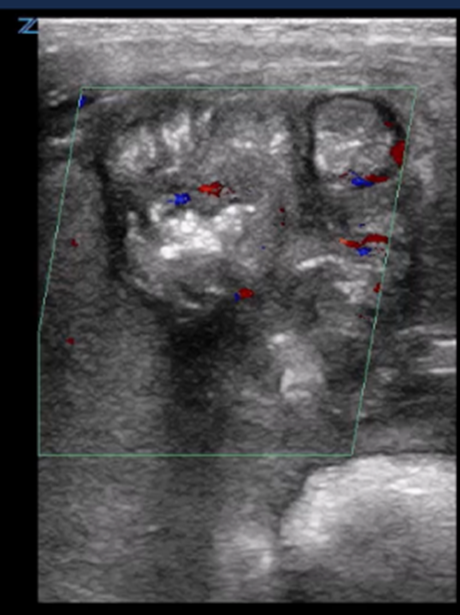

| Hyperemia by colour Doppler | |

| Strengths | Considerations |

|

![]() ![]() |

First: Normal intestinal image shows 3- to 9-colour speckled pattern indicating normal perfusion Second: Hyperemia with a Y pattern |